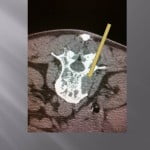

Biopsie sous guidage scanner